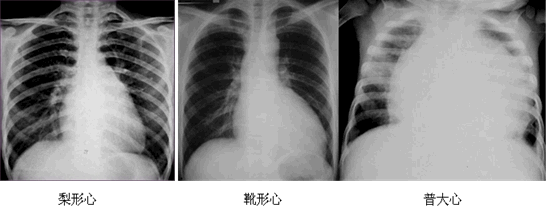

| 二尖瓣型 | 梨形心 | 左心房增大 | 二尖瓣狭窄(最常见) |

| 主动脉型 | 靴形心 | 左心室扩大 | 法洛四联征、主动脉瓣膜疾病、高血压心脏病等 |

| 普大型 | 普大心 | 心界向两侧扩大 | 心肌病、心脏病后期、心包积液等 |